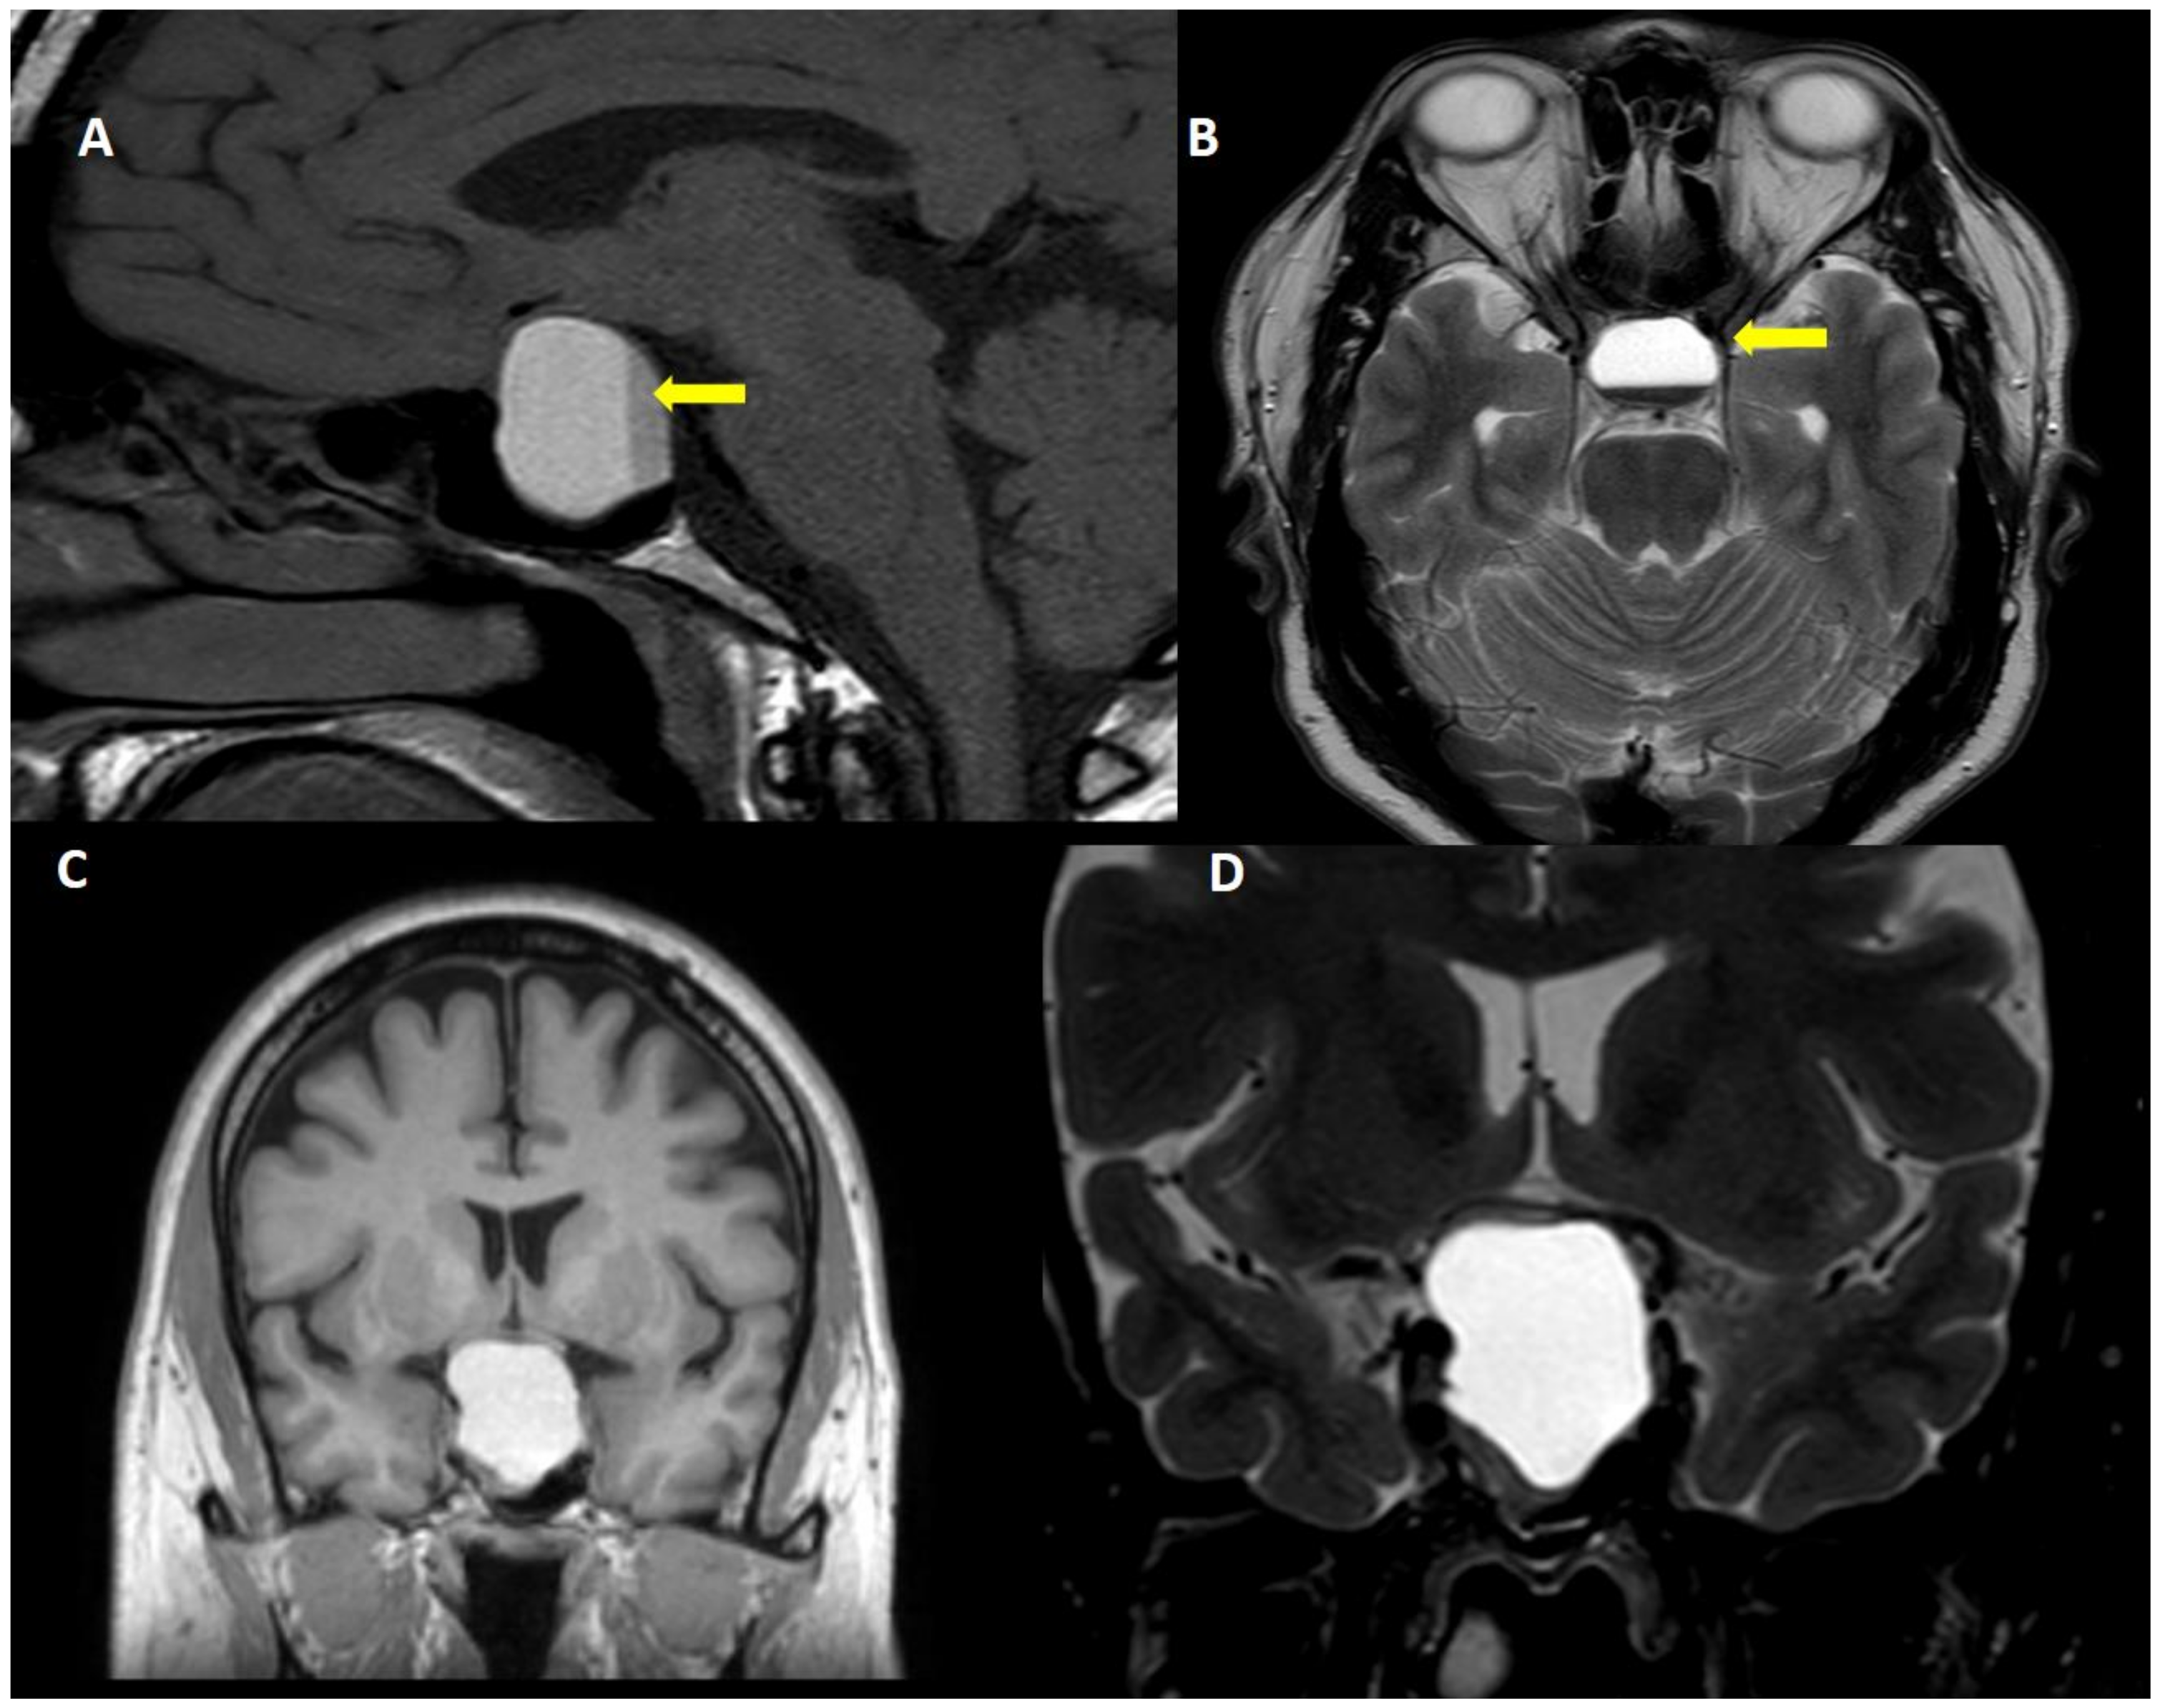

- Puglisi, V.; Morini, E.; Biasini, F.; Vinciguerra, L.; Lanza, G.; Bramanti, P. Neurological Presentation of Giant Pituitary Tumour Apoplexy: Case Report and Literature Review of a Rare but Life-Threatening Condition. J. Clin. Med. 2022, 11, 1581. [Google Scholar] [CrossRef]